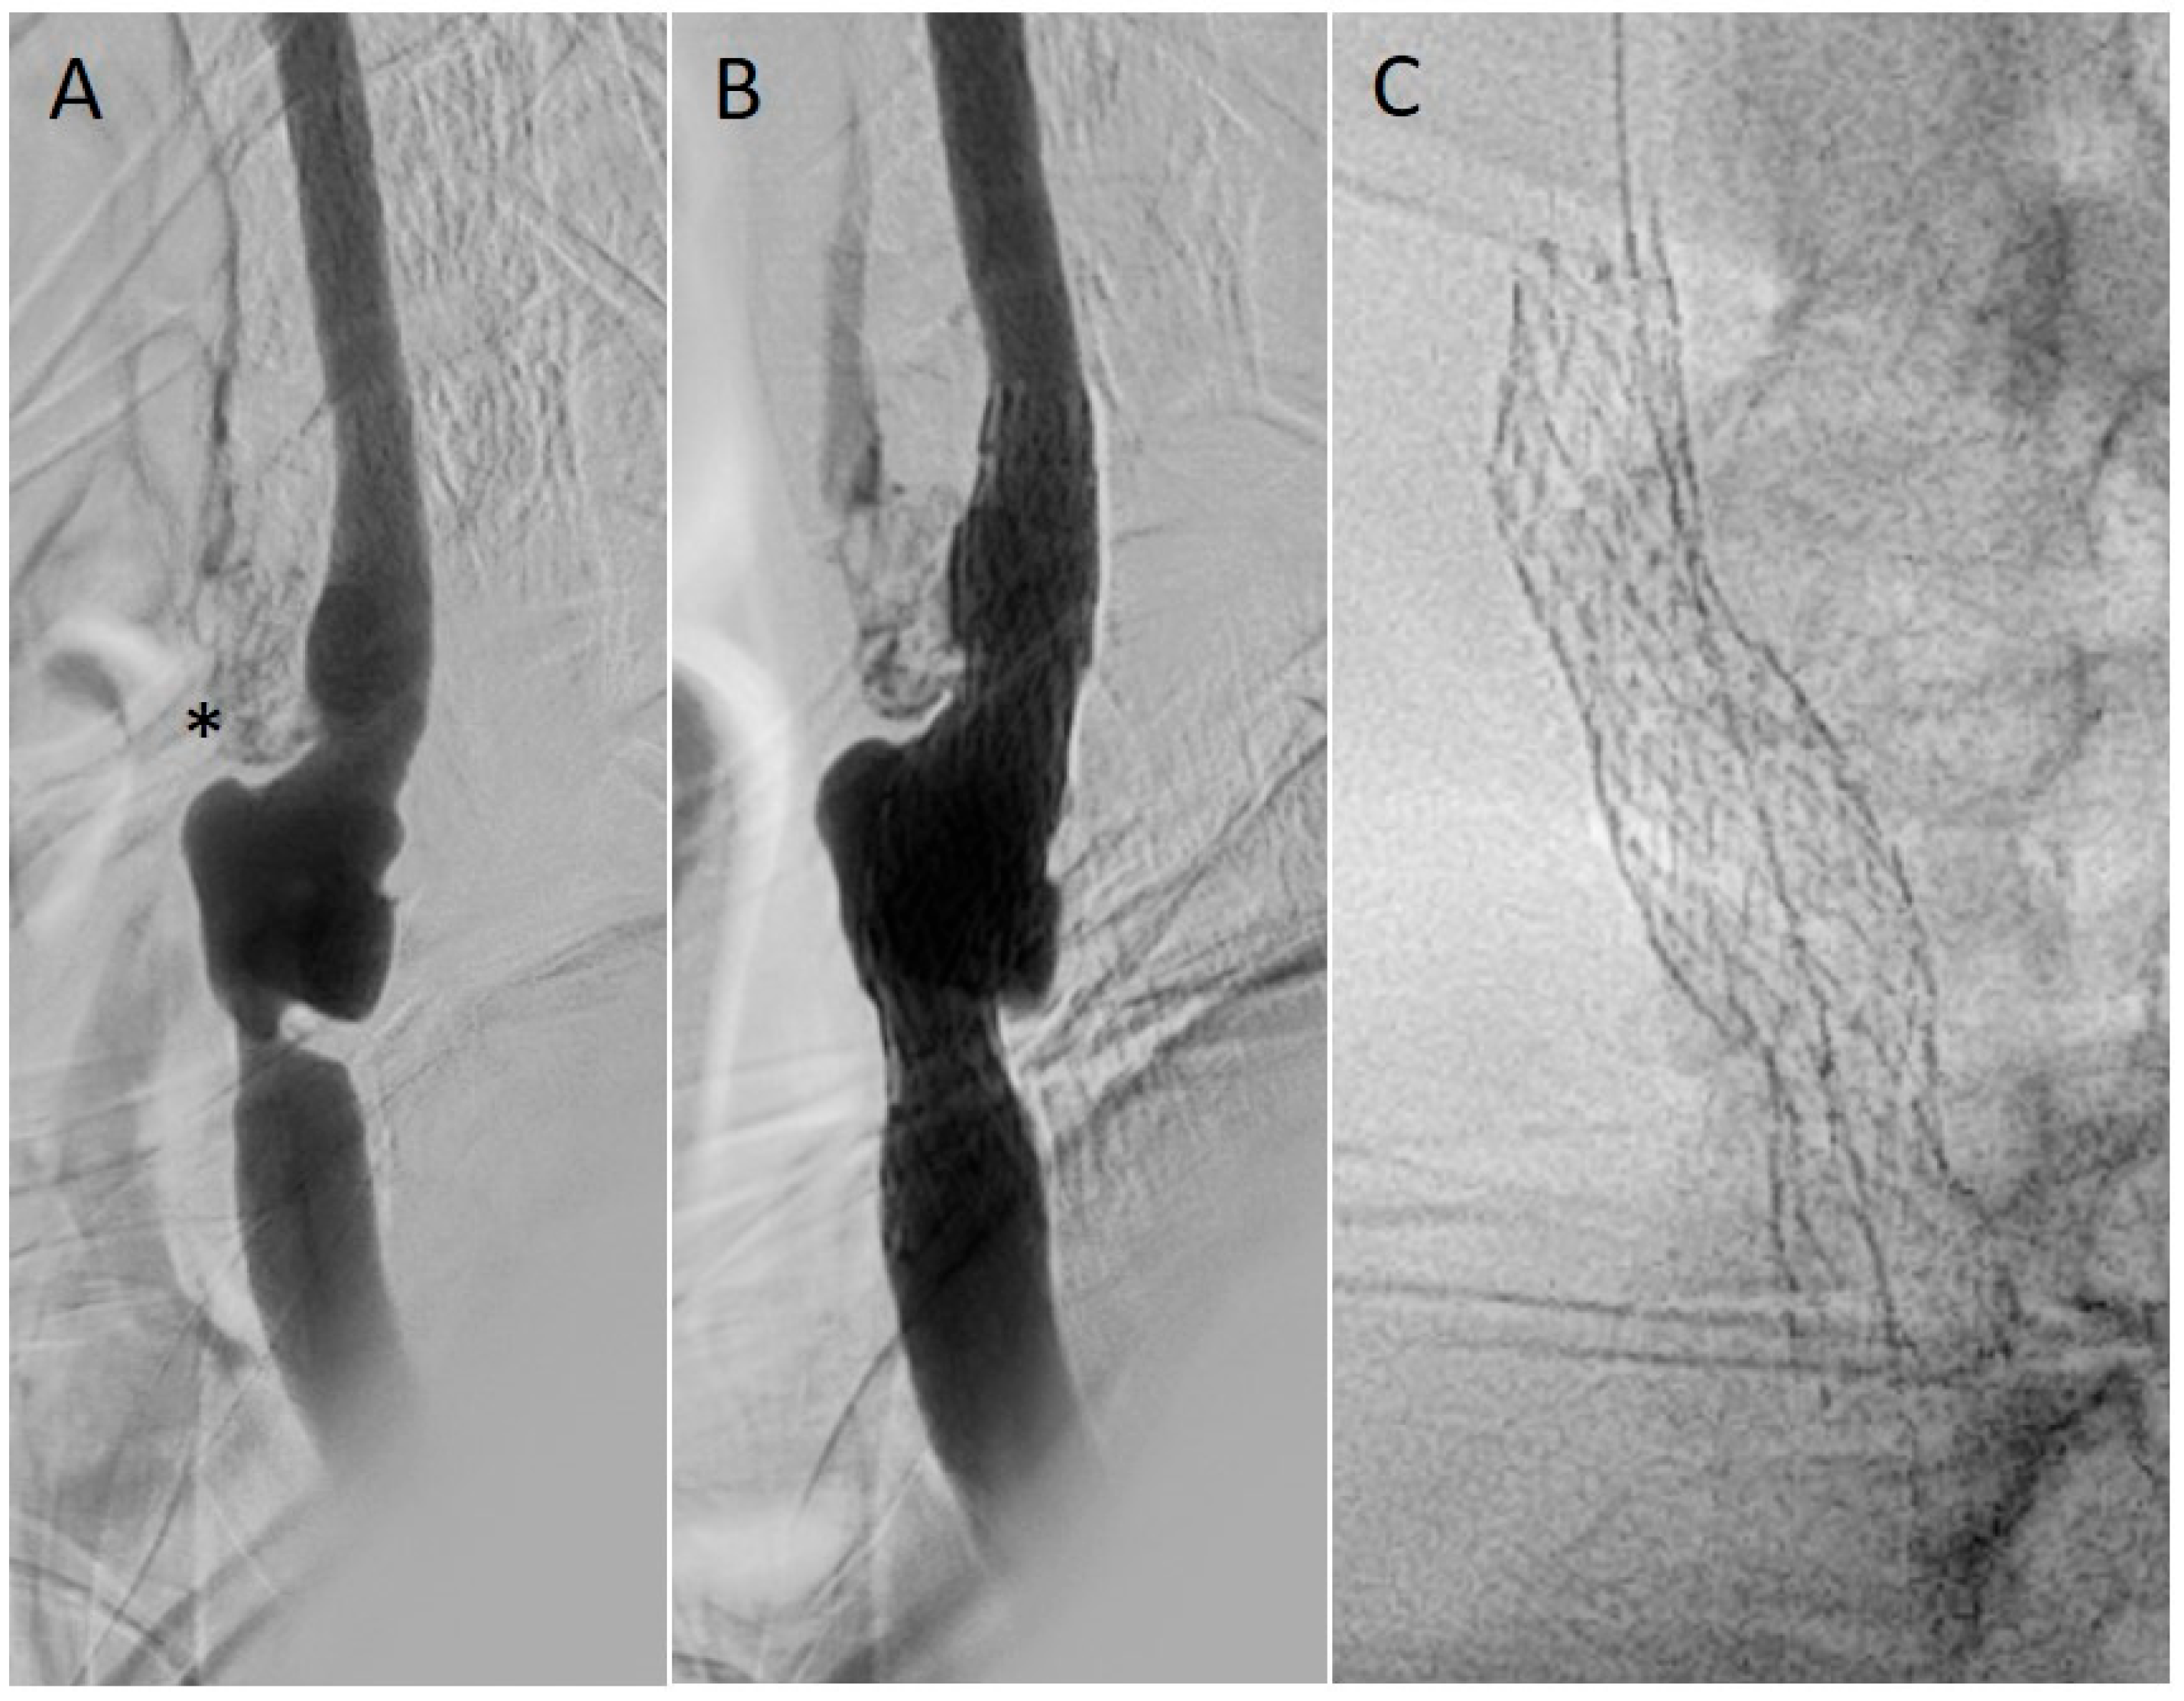

8.2.2. Re-Stenting (Stent-in-Stent CAS)